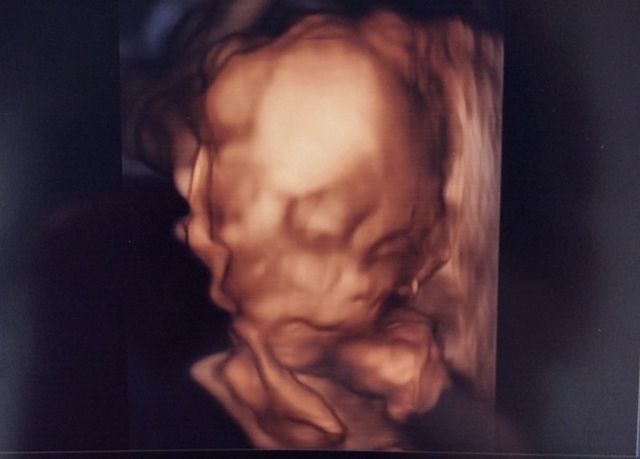

24週5日(24w5d・男の子)|mayumi817 さん(32歳)

エコー写真撮影時のエピソード:

10年振りの妊娠 今のエコー技術はスゴかった! とてもキレイに取れててビックリしました。 顔立ちはやっぱりお姉ちゃん似⁉︎それともパパ似かな(笑)

今のところすごく赤ちゃんも体調も順調☆ ただ、体重管理が難しいね…。 この時からだいぶたって只今9ヶ月もうすぐ会えるね(﹡ˆ﹀ˆ﹡)♡